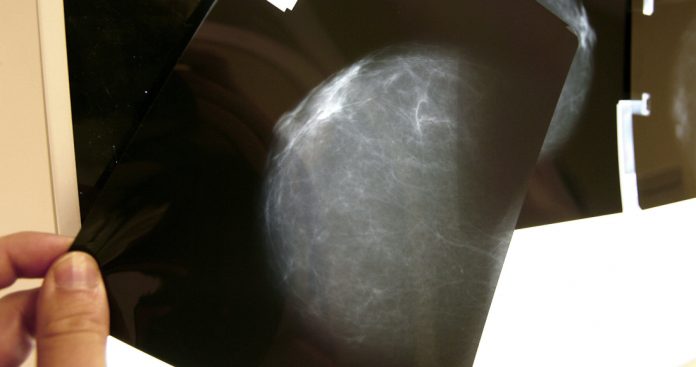

En la lucha contra el cáncer de mama, el tumor más frecuentemente diagnosticado entre las mujeres, se siguen dedicando grandes esfuerzos para desarrollar nuevos tratamientos que ayuden a aumentar el arsenal disponible.